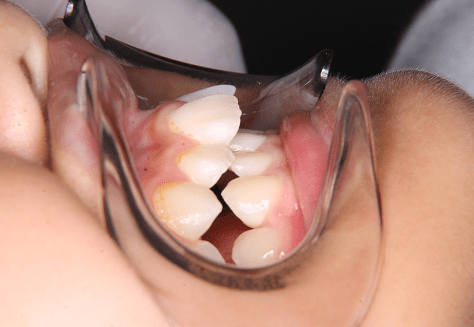

M.H

治療前

治療後

主訴

前歯が出ている。下の歯並びが特に気になる。奥歯でしっかり噛めない。

診断

上顎前突・叢生・シザーズバイト

年齢/性別

20代/男性

抜歯部位

下顎両側大三大臼歯(口腔外科にて)

上顎両側第一小臼歯・下顎左側側切歯

(当院にて5,500円×3) -

使用装置

上下エッジワイズ→インビザライン(PBM使用)

保定装置

上下ビベラリテーナー

基本料金

880,000円

診察料金

5,500円×44回

治療期間

3年6カ月